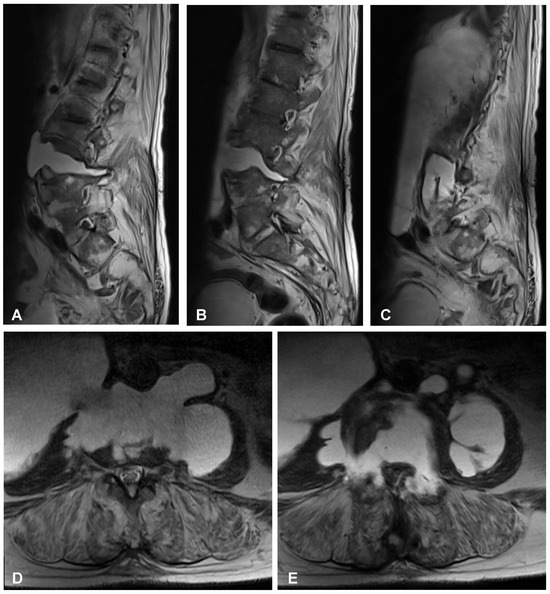

Figure 4. Preoperative sagittal (AC) and axial (D,E) MRI scans (T2-weighted images) of the lumbar spine demonstrating high-intensity area at the L3/L4 intervertebral disc space communicating with both psoas major muscles forming massive well-defined fluid collection in the right retroperitoneum.

A 59-year-old man presented to the hospital with atypical abdominal pain for a few days, three weeks after sustaining a low-energy fall. At the time of admission, the patient had normal upper and lower extremity strength and no pathologic reflexes, as well as no bowel or bladder incontinence. The initial performed plain radiograph of the abdomen demonstrated a fracture line completely slicing through the L3/L4 intervertebral disc space and features of ASH (Figure 1). The additional performed computed tomography (CT) scans demonstrated a three-column fracture of L4 vertebrae with a suspicious transdiscal injury at the L3/L4 level, which was morphologically classified as type B3/C according to the Arbeitsgemeinschaft für Osteosynthesefragen (AO) spine classification. Moreover, at the fracture level, the hypodense area communicating intervertebral disc space with both psoas major muscles forming a massive, well-defined fluid-like collection in the right retroperitoneum was observed (Figure 2). In addition, contrast-enhanced CT (CE-CT) showed a thick enhancing wall and internal septae within an area measuring a total of 10 cm × 20 cm × 10 cm (TR × AP × CC) (Figure 3). Furthermore, the performed magnetic resonance imaging (MRI) scans confirmed the cystic nature of the lesion, which had no specific characteristics and demonstrated intensities that were similar to those of cerebrospinal fluid (CSF) (Figure 4). Taking into consideration the history and radiological features, suspicion of spondylodiscitis with osteomyelitis features and retroperitoneal abscess formation was provided by the radiologist. Blood analysis performed on admission revealed the following results: hemoglobin (Hb): 9.6 g/dL; platelet (PLT): 192 × 109/L; white blood cell (WBC): 9.7 × 109/L; and creatinine (CREA): 0.42 mg/dL. Despite the lack of infection symptoms, the patient was empirically administered intravenous antibiotics, including meropenem (1 g every 8 h) and vanomycin (1 g every 12 h), without waiting for microbiological confirmation.